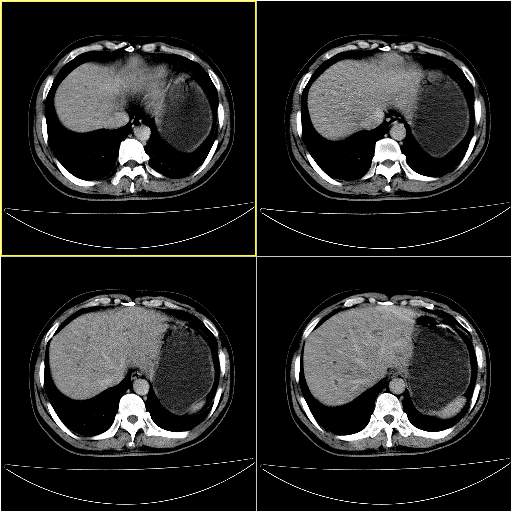

男性,54岁,皮肤黄染,搔痒一周余.b超示肝左叶回声异常.初步诊断1胆总管下段结石2胆囊结石伴慢性胆囊炎请各位战友帮忙看一下肝脏多发低密度如何解释恰当.增强效果不是很好.请大家见谅.

胆总管及肝内胆管扩张,考虑是结石!但,肝内的低密度区增强不明,可能是肝ca,因为肝ca在增强时呈快进快出.另年胆总管扩张原因,可以考虑一下是不是,胆管ca.再次要考虑肝内的低密度是否为海绵状血管瘤所致!

其次,增强动脉期肝静脉显影,肝实质密度不均。——此为右心功能不全引起肝淤血的表现。

另外,肝八段低密度占位,呈多灶性,考虑肝脓肿或肝癌可能,(图像质量欠佳)建议进一步检查。

既然做了增强,为什么光提供延时期片子,肝动静脉期肝右叶前下段病灶增强如何?另外胆囊壁增厚,欠规整,内密度不均,与肝右叶病灶分界不清,增强表现怎样?肝内胆管轻度扩张,胆总管扩张,但未见明显结石影,也应提供增强早期图像才好鉴别扩张原因。片子较清,但不够完整,暂考虑1.胆囊癌肝局部浸润,或肝癌胆囊侵犯,2.胆总管下端或胰头钩突部占位。总之本人看不明白,请高手画图指示,先谢了!

由于胆囊窝内结构显示不清,肝脏病灶又邻近胆囊窝首先考虑胆囊癌肝受侵犯。而后因肝脏病灶强化有渐进改变,且相邻胆管扩张,故考虑肝胆管细胞癌待排。

左肝胆管细胞癌。

胆总管下端结石。